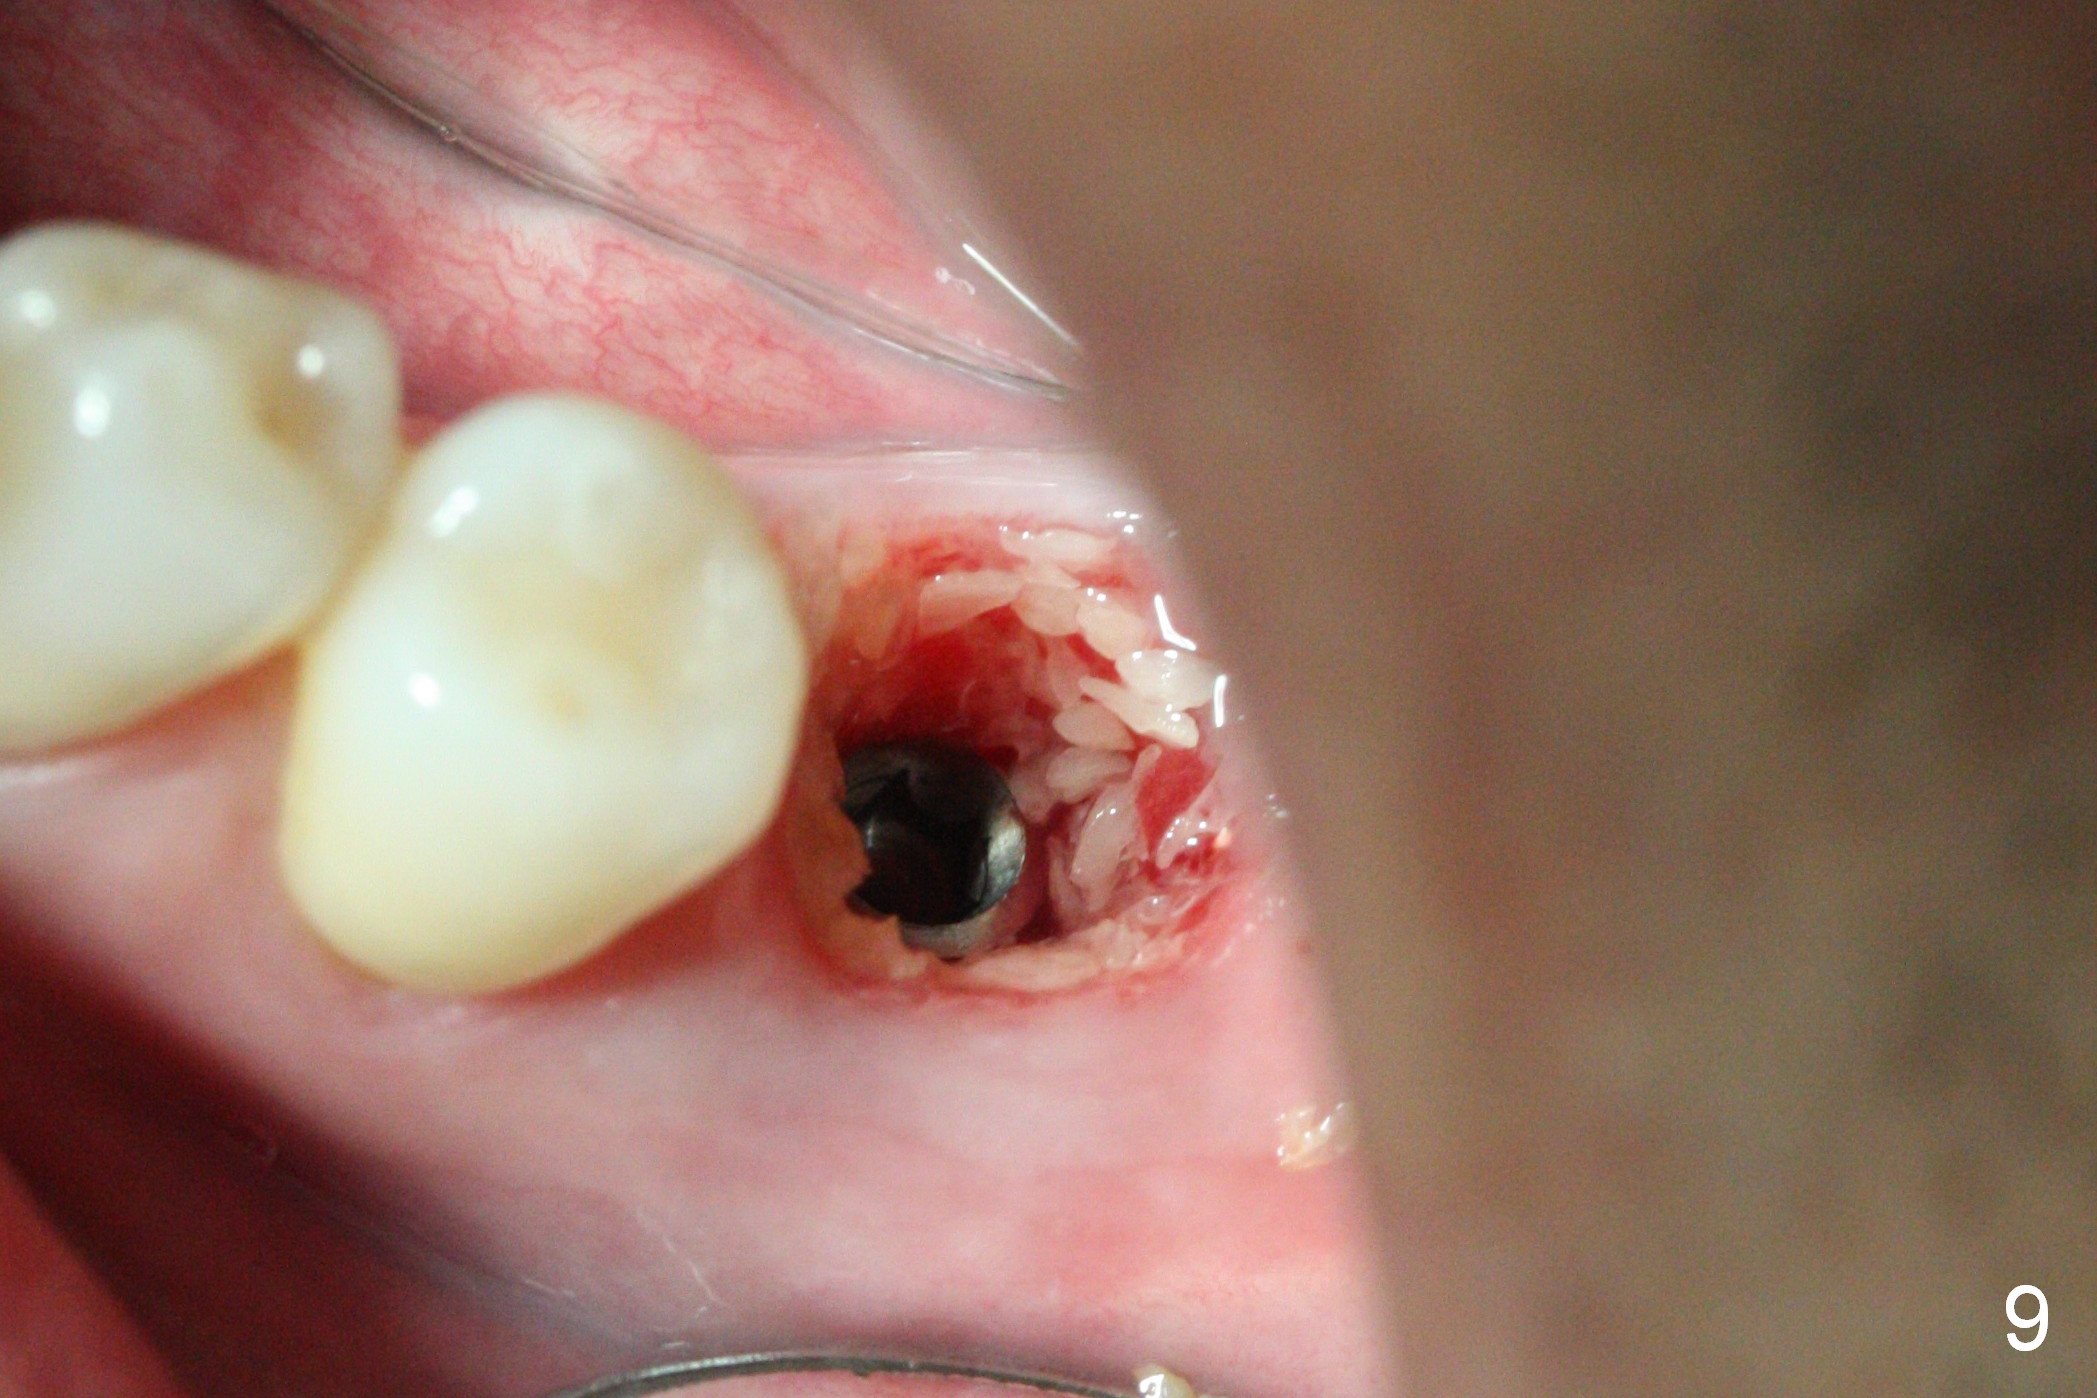

The tooth #19 is easy to get loose, but it cannot be luxated.  After sectioning and extraction (Clindamycin), the septum is found to be thin (Fig.4).  A surgical fissure bur is used to initiate osteotomy, followed by 1.6 mm pilot drill.  It is difficult to use Marking bur (wobbling over the basically pointed septum).  It is impossible to use 4.3 mm Magic Drill (MD, one drill system), since it jumps.  The smallest MD has to be used (2.8 mm).  When the next drill (3.3 mm) is being used for 13 mm with stopper (Fig.5), the patient experiences transient pain.  The depth is suggested from the design in Fig.2.  The thin septum appears not to be a reliable landmark.  When block anesthesia is administered, the initial depth should be shortened.  The drill appears to be close to the Inferior Alveolar Canal (Fig.5).  Then the depth changes to 11 mm with the following drills (3.8 and 4.3).  The mesial and distal walls of the septum are gradually perforated.  A 5x9 mm dummy implant is placed only after using 4.8 mm drill (Fig.6).  The implant appears to be short.  When a longer implant is placed (5x11 mm), it does not easily enter the osteotomy, either sliding into the mesial or distal socket with the implant separating from the implant driver.  It appears that a premount implant is appropriate in this situation.  When the 5x11 mm implant is finally seated with stability, it is 6 mm apical to the gingival margin.  The longest cuff of IBS abutment is 4 mm.  A longer implant is needed (Fig.7, 5x13 mm).  Placement is not easy as mentioned above.  Insertion torque is <20 Ncm when the patient experience a little discomfort.  A 6.5x4(4) mm pair abutment is placed (A), apparently proper for restoration.  Allograft is placed (Fig.8 *) prior to immediate provisional.  The patient complains of bad smell from the site 24 days postop.  When the provisional is removed, the abutment is found to be mobile.  When the latter is removed with local anesthesia, bone graft granules are attached to the socket above the lightly mobile implant (Fig.9).  In fact the latter appears to be stable after a few turns by finger.  A healing screw is placed; the socket is closed with collagen plug and 4-0 Chromic gut sutures (Fig.10).  It appears that a larger implant should have been used to achieve higher torque.  Two months later (3 months postop), the coronal end of the implant is partially exposed.  A 5x4 mm healing abutment is placed.  It appears that the implant is stable.  The implant appears to have osteointegrated 4 months postop (Fig.11).  Impression is taken.